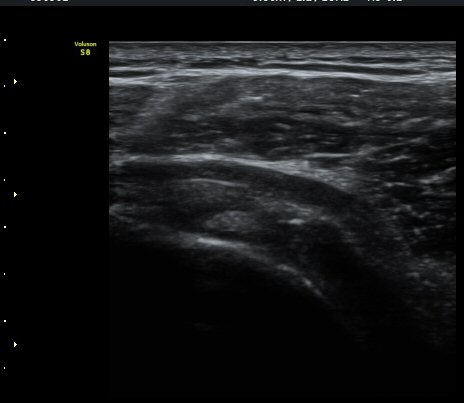

±Ø»ó°Ç Á¾´Ü¸é°Ë»ç¿¡¼­ Á¤¸Æ³¶³» ¼ö¾×Àú·ù¿Í ±Ø»ó°Ç³» ¼®È¸È­À½¿µÀÌ °üÂûµÈ´Ù(±×¸² 2, 3).

±Ø»ó°Ç ¸»´ÜºÎ Á¾´Ü¸é°Ë»ç¿¡¼­ ±Ø»ó°Ç°ú Á¡¾×³¶³» ¼®È¸È­°¡ °üÂûµÈ´Ù(±×¸² 4, 5).